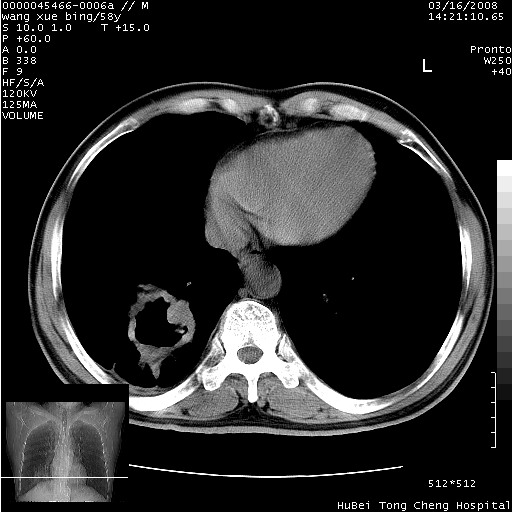

患者 男,58岁。咳嗽、咯血3月余。

胸部ct轴位平扫(层厚10mm,螺距1.5,重建间隔10mm),图像如下:

右肺下叶团块及不规则空洞,内壁不规则,外缘见粗长毛刺,临近胸膜明显增厚并与病灶关系密切。支持考虑:右肺肺脓肿!建议穿刺病理检查待除外周围型肺癌!

右肺下叶见不规则厚壁空洞,内壁不规则,外缘见粗长毛刺,临近胸膜明显增厚并与病灶关系密切。支持考虑:周围型肺癌!

考虑右下肺中心型肺癌并远端阻塞性炎症及胸膜及纵隔淋巴转移

右肺下叶周围型肺癌伴空洞形成!征象比较明显!分叶、毛刺、胸膜凹陷征、厚壁空洞,壁结节!

影像符合癌性空洞表现,临床如无咳大量浓臭痰史,还是考虑周围型肺癌可能性大。

空洞壁厚,不规则,其内可见壁结节,周围可见毛刺及阻塞性炎变,多考虑癌性病变.